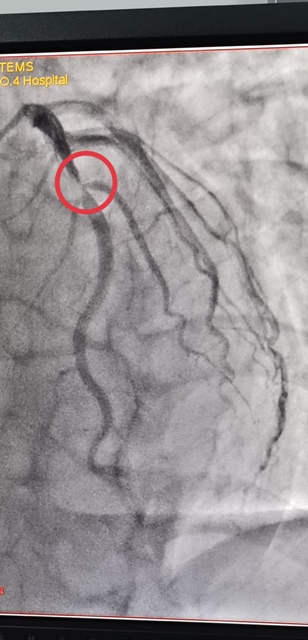

45岁的郭先生,一周前无明显诱因出现胸前区疼痛,伴有胸闷、心悸,疼痛发作时间持续10分钟后自行缓解,伴有大汗淋漓,来亚色视频 心血管内科就诊诊断为“冠心病不稳定性心绞痛”,于2021年1月3日早上10点进入导管室,实施了冠脉造影术 经皮冠状动脉内支架植入术,心内科主任王选琦主任医师介绍说,这是省四院第一例648元支架手术,手术进展顺利,患者术中、术后无不适症状,术后病症明显缓解,目前在心内科治疗观察。

陕西省第四人民医院于2021年1月1日零时执行国家组织冠脉支架集中带量采购中选结果,据悉,中选的冠脉支架产品的平均价格由原来的7500元降至648元。为确保患者在2021年1月1日当天能够使用中选产品,陕西省第四人民医院迅速贯彻省市医保局要求,已经将中选支架采购安排到位,从2021年1月1日0时开始实施新的价格标准。郭先生是蓝田人,成为新年第一个享受国家医改福利的人。